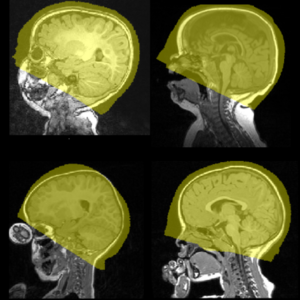

PICASSO ; MASS: brain MRI skull stripping, for

- 0-100 years

- multi-site clinically-acquired as well as research brain MRI;

- T1, MPRAGE and diffusion (ADC map) MRI;

- multi-scanner (GE, Siemens, Philips) and multi-platform (1.0T, 1.5T, 3T, 7T) brain MRI;

- healthy as well lesion-bearing (e.g., brain tumor, cavity-bearing) brain MRI.